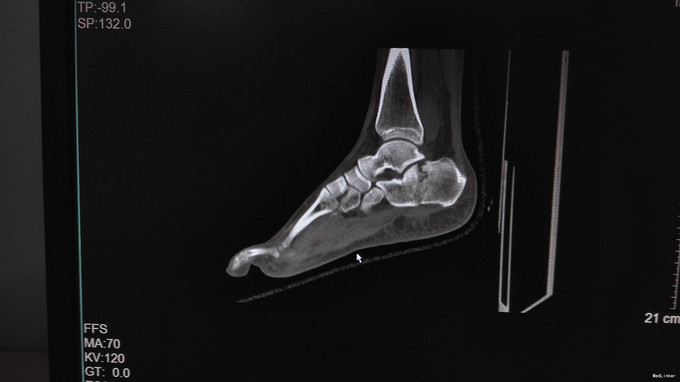

左足跟淤血肿胀明显,无明显畸形,皮肤完整,局部压痛明显,可扪及骨擦感,纵向叩击痛阳性,足趾活动正常,末梢血运、感觉正常。左跟骨X片示:左跟骨粉碎性骨折,左足部CT示:左侧跟骨粉碎性骨折,累及跟距关节面。

左跟骨粉碎性骨折,排除手术禁忌症后行左跟骨粉碎性骨折切开复位内固定术。

中年男性患者,因“跌倒致左足跟部疼痛、活动受限4小时”入院,左跟骨X片及左足部CT提示:左跟骨粉碎性骨折,累及跟距关节面。结合临床症状、体征及影像学检查,诊断左跟骨粉碎性骨折,且累及关节面,手术指征明确,排除手术禁忌后行切开复位内固定术,术后复查X片示对位良好。出院1月后复查,1月内避免负重。